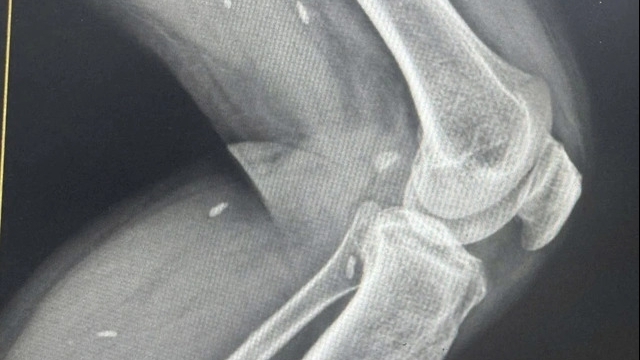

![]() |

| Ảnh minh họa |